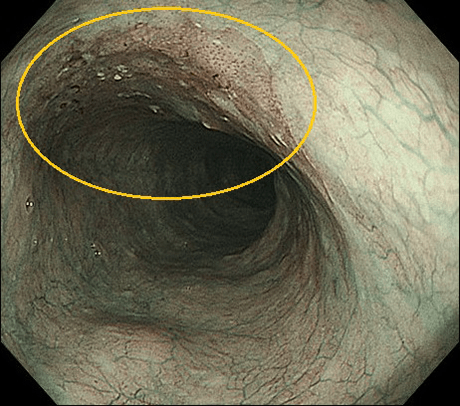

NBIの有用性を実際の内視鏡写真でお示しします。

食道の場合

通常光(白色光)

NBI

NBI(拡大)

通常光では血管透見が消失したやや発赤した領域として描出されますが、視認は困難です。NBIでは明瞭な茶褐色の領域として病変を描出することが可能となります。

さらに拡大観察を行うことで、早期の食道がんで内視鏡治療の適応と診断することが可能となります。